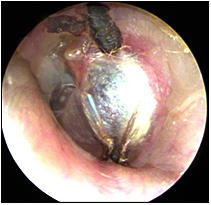

JFC Otitis media supurativa crónica. Colesteatoma.

JFC Otitis media crónica colesteatomatosa.